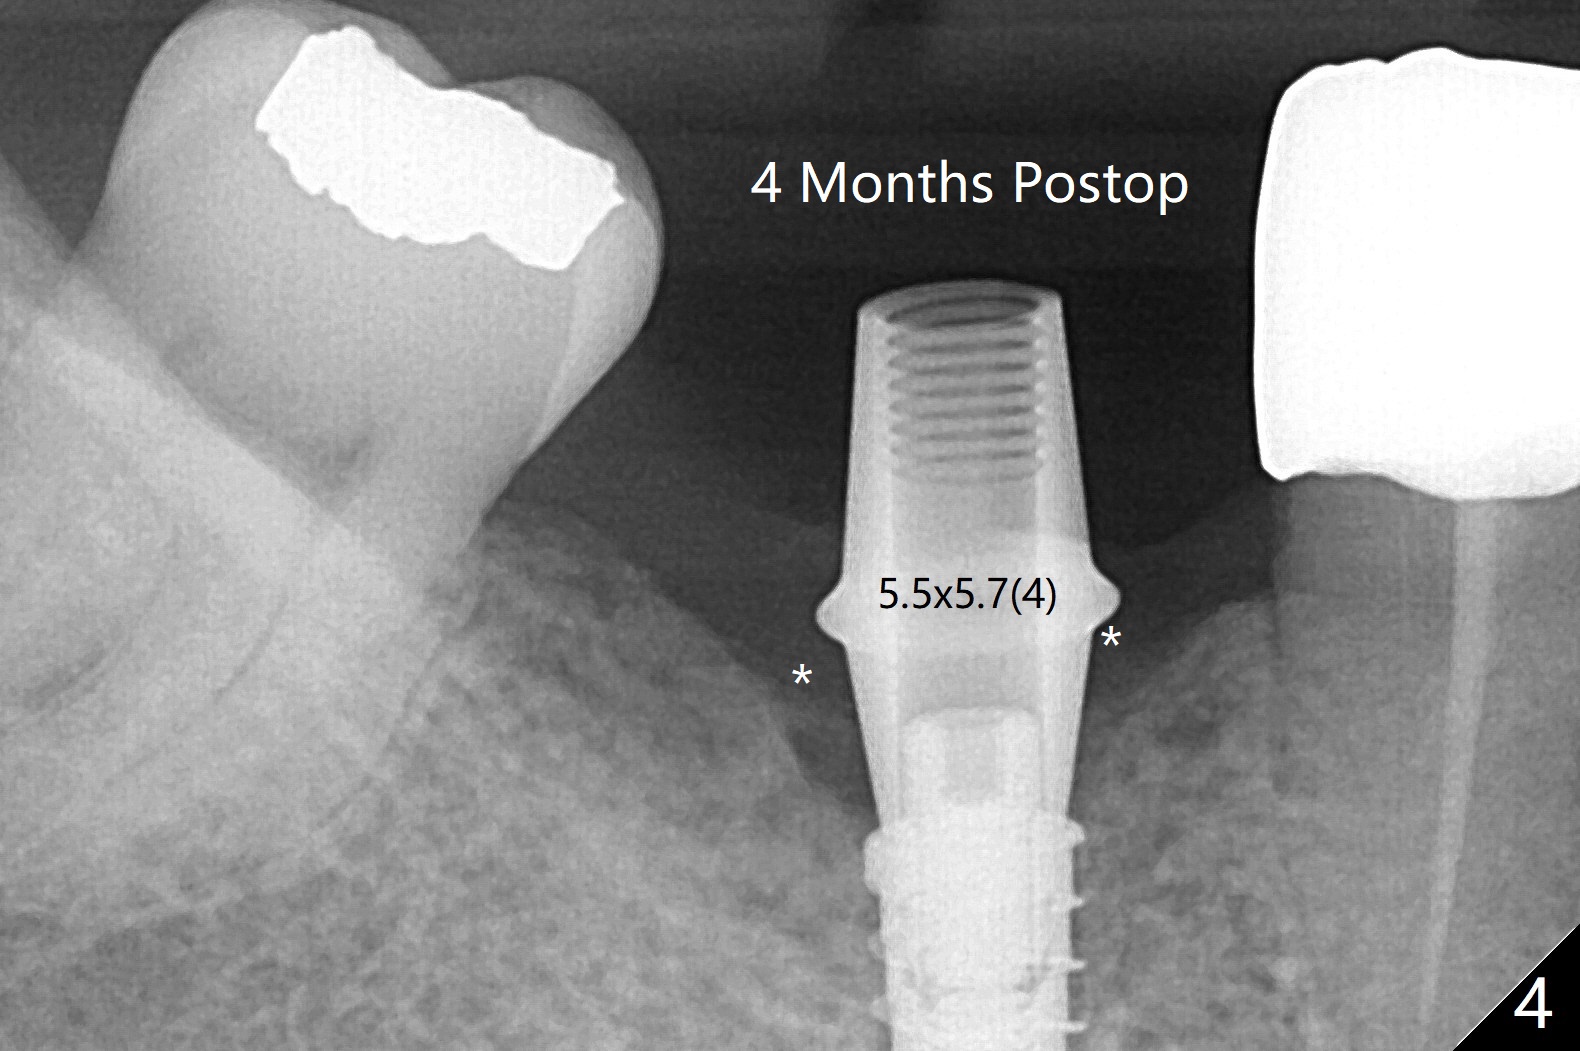

Since the preop ridge looks narrow at #30, incision is made, which makes it easy for observation of osteotomy. First, a 10.5 mm bone trimmer makes a deep dimple with apparently moderate ridge wide enough for a 4 mm implant. The patient has hypertension and cannot lie down for long. The bone density feels not high; a 4x11 mm (instead of 9 mm) implant is placed for 10 mm osteotomy (Fig.1 (~ 35 Ncm)). After use of 6 mm bone profile drill, there is bone buccal (less) and lingual to the implant. A 5.5x4 mm healing abutment is inserted, barely supragingival. As the implant is 1 mm longer than the design, regional panoramic X-ray is taken to determine clearance from the Inferior Alveolar Canal (Fig.2 red dashed line (the upper border). There is crestal bone loss 4 months postop (Fig.3,4). It appears that the implant was placed excessively deep. There is no implant thread exposure 9 months post cementation (Fig.5,6).